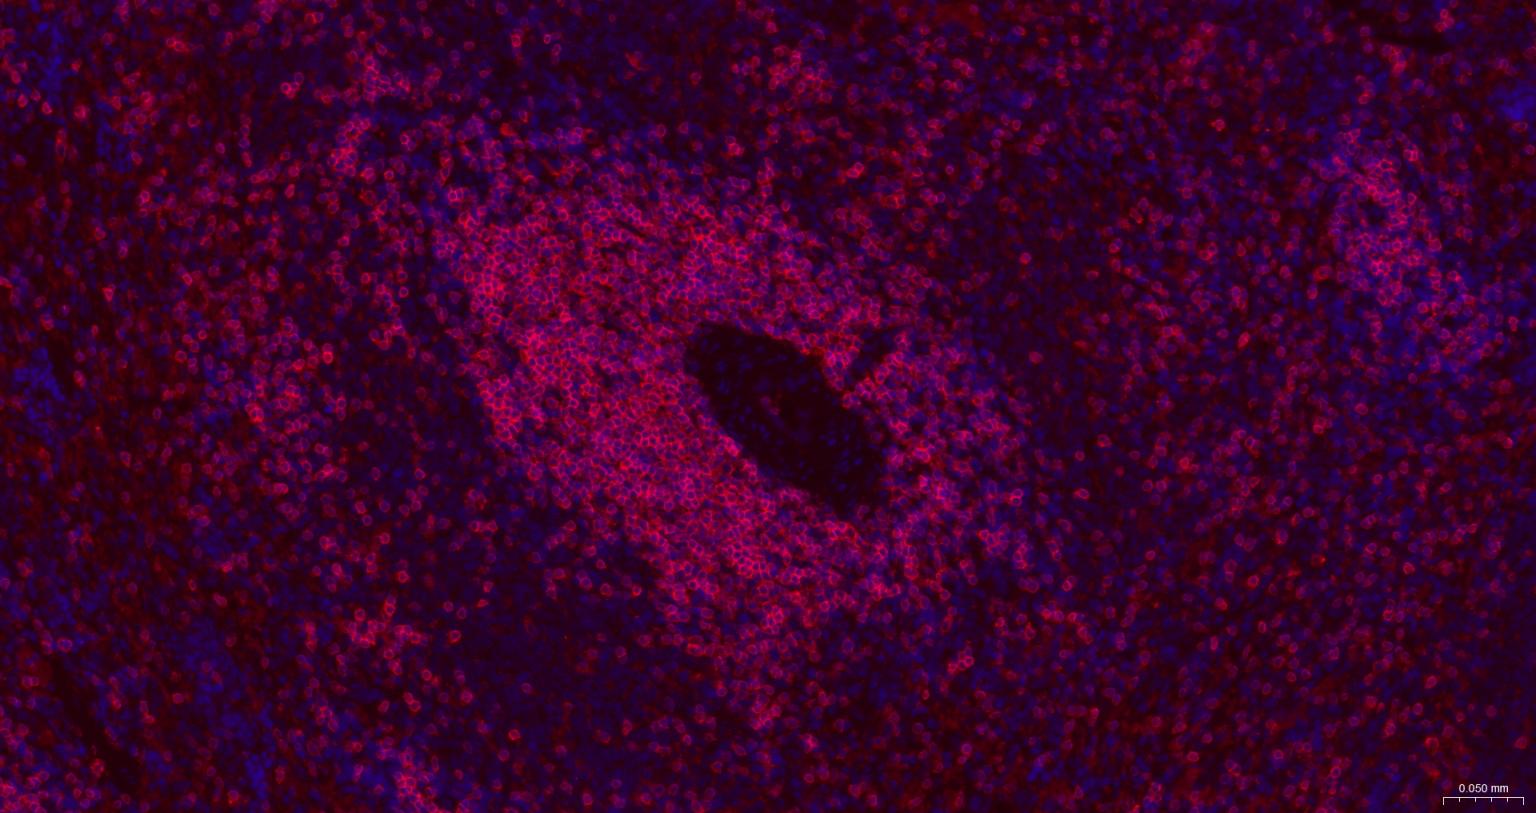

Paraformaldehyde-fixed, paraffin embedded Rat Spleen; Antigen retrieval by boiling in sodium citrate buffer (pH6.0) for 15 min; The section was incubated with CD3E Monoclonal Antibody, Unconjugated (bsm-60002) at 1:500 overnight at 4°C. Followed by conjugated Goat Anti-Rabbit IgG antibody (Red, bs-0295G-BF594), DAPI (blue, C02-04002) was used to stain the cell nuclei.